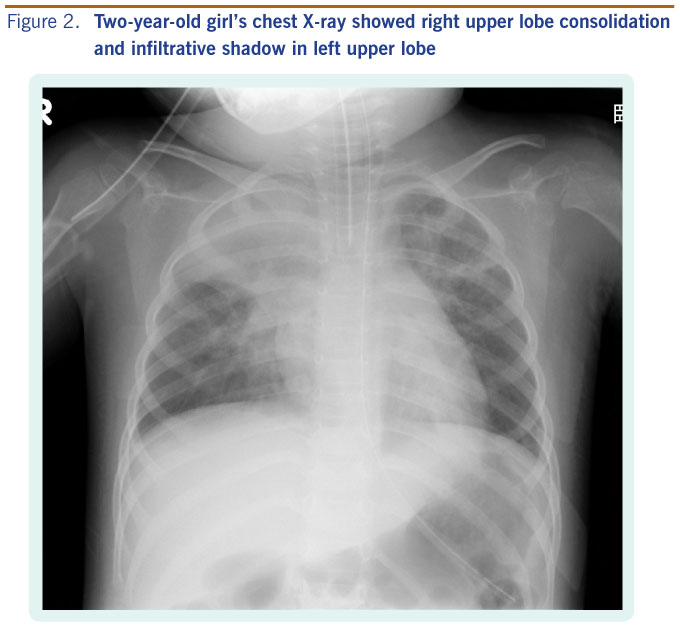

Chest pain when you breathe or cough. When both lungs are affected the condition is called. Sala says that the only way to confirm a diagnosis of pneumonia is to visit a doctor to get an x ray and physical exam.